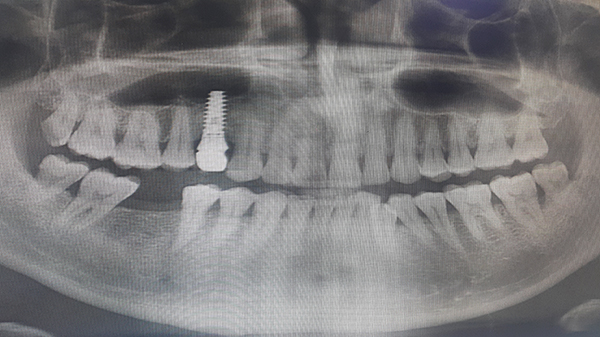

임플란트 치료 기간의 가장 중요한 포인트는 바로 잇몸뼈의 여부입니다. 만약 잇몸뼈가 충분하다면 일반적으로 3~4개월 정도면 충분할 수 있는데, 잇몸뼈가 부족하다면 뼈이식을 해야 하므로 기간이 더 길어질 수 있습니다. 잇몸뼈가 부족한 경우 뼈이식 수술을 통해 잇몸뼈를 보강해야 하며, 이는 임플란트 치료 기간을 6개월 이상으로 연장할 수 있습니다. 따라서 초기 상담 시 잇몸뼈 상태를 정확히 진단받는 것이 중요합니다.

또한, 임플란트의 위치에 따라 치료 기간이 달라지는데, 상악의 경우엔 5개월 ~ 6개월 정도가 소요되고, 하악의 경우 3개월 ~ 4개월 정도가 소요되는 것이 일반적입니다. 하악은 상악에 비해 치조골의 밀도가 높다 보니 하악 쪽이 치료 기간이 더 단축되는 것입니다. 상악의 경우 부비동이 가까워 추가적인 뼈이식이 필요한 경우가 많아 치료 기간이 더 길어질 수 있습니다.

만약 임플란트를 해야 할 치아가 여러 개라면 치료 기간은 더 늘어날 수 있습니다. 또한, 당뇨나 골다공증 같은 전신질환을 가지고 있으면 회복이 더디거나 염증이 발생할 수 있어 치료 기간은 더 길어질 수 있습니다. 전신질환이 있는 환자는 치료 전 충분한 상담과 진단이 필요하며, 이에 따라 치료 계획이 수정될 수 있습니다.